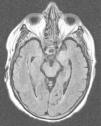

Hereby we present the clinical case of a seventy one year old female with dyslipidemia, hypothyroidism and breast ductal carcinoma with radical exeresis and treated with chemotherapy. She was admitted in the hospital following an event of sepsis due to methicillin-sensitive Staphylococcus aureus (due to reservoir infection). She suffers from progressive disorientation, repetitive talking, and sleepiness with progression towards status epilepticus, which is why she was admitted in the unit of intensive care medicine (ICM). The urgent cranial computed tomography (CT) scan performed did not show any significant findings. At admission her state is post-critical after the administration of intravenous (IV) benzodiazepines and her temperature is 38°C; the rest of the device based-medical examination was normal. The blood sample showed platelet levels of 22×109/l, creatinine levels of 3.5mg/dl, urea levels of 95mg/dl, C-reactive protein (CRP) levels of 15.6mg/dl, the rest being normal. Doctors proceeded with orotracheal intubation and lumbar puncture (LP) followed by secretion of cerebrospinal fluid (CSF) colourless at normal-pressure without cells, glucose levels of 68mg/gl and protein levels of 64mg/dl (plasma proteins 5.2g/dl). Doctors proceeded with sedoanalgesia, fluid therapy, levetiracetam, and broad-spectrum IV antimicrobial treatment including acyclovir. They were isolated in bronchoaspiration and one hemoculture of the extended-spectrum-beta-lactamase-producing Klebsiella pneumonia without condensation in the chest X-ray was collected; both the urine culture and the CSF culture tested negative. CSF with polymerase chain reaction (PCR) for herpes simplex virus (HSV), cytomegalovirus (CMV), varicella zoster virus (VZV) and Epstein–Barr virus (EBV) all tested negative, and the cytology to rule out malignant cells tested negative too. Serologies for human immunodeficiency virus (HIV), hepatitis, HSV, CMV and VZV tested negative for active infections. Elevated CA 125 level (180.3U/ml); remaining tumour markers normal. Negative test results for the anti-DNA antibodies, antinuclear antibodies, c-ANCA and p-ANCA. Thyroid hormones in normal ranges with replacement therapy and negative test results for the antiperoxidase and antithyroglobulin antibodies. One second CT scan with the administration contrast is performed and it rules out structural disease, and also another control LP with secretion of colourless fluid at normal pressure with normal biochemical profile without cells, and negative for malignancy. Given the low level of consciousness, one electroencephalogram (EEG) is performed that is consistent with the effects of sedation and the nuclear magnetic resonance (NMR) of the brain with the following results: in the T2-weighted sequence of the hypocampic region, there is hyperintensity of left predominance, in the diffusion-weighted sequence, there is hyperintensity and a mild decrease of the apparent diffusion coefficient (ADC) in the hypocampic region of the left temporal lobe. After the administration of paramagnetic contrast there is no presence of any uptakes (Figs. 1 and 2A and B).

The clinical manifestations of LE are the subacute2 appearance of several neuropsychiatric alterations including, among others, cognitive impairment, seizures, depression, irritability, hallucinations, and loss of short term memory.3,4 In most cases, the CSF5 shows inflammatory changes with discrete proteinorrachia and/or pleocytosis without pathognomonic findings. The CT scan5 is usually normal, without contrast uptake, while in 70% of the cases, the NMR of the brain5 is asymmetrically hyperintense in both temporal lobes, especially the T2 and the FLAIR-weighted sequences, while remains unenhanced after the administration of contrast. The EEG can show temporal or diffuse slowness, temporal spikes, and temporal or generalized focal seizure activity.